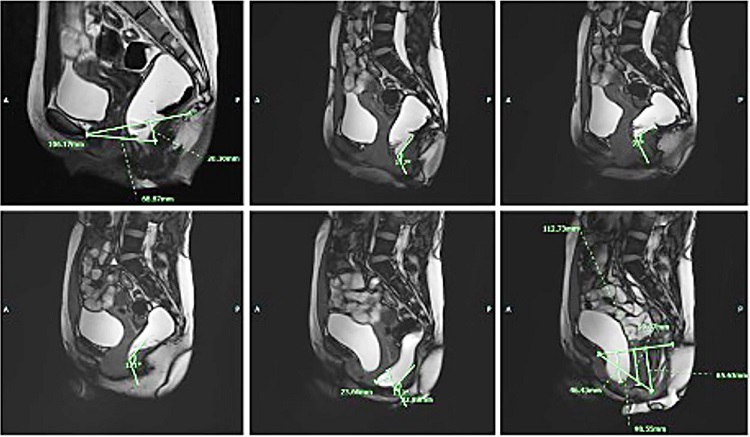

At our institution, an X-ray gastrografin enema was performed, showing ahaustral mucosal appearance of the sigmoid and descending colon (Figure 2). MRI defecography was also done with findings suggestive of tricompartmental pelvic floor prolapse, moderate size anterior rectocele, and grade 2 sigmoidocele (Figure 3).

No findings are pathognomonic for intestinal duplications on imaging. Work up can begin with plain chest and abdominal X-rays and can be followed by a CT scan. Ultrasonography, barium enema, and colonoscopy can also aid in the diagnosis. Yet, they might not always yield a definitive diagnosis.16 Indeed, due to the non-specificity of their results, it is difficult to make a pre-operative diagnosis. In our case, colonoscopy showed that the entire examined colon appeared normal on direct and retroflection views, failing to demonstrate the communicating duplication with the colonic lumen. This might be due to the impaction of the duplication with stool, hindering its visualization on colonoscopy despite it being wide-based. Abdominal CT findings were non-specific, revealing a diffusely mildly dilated redundant colon, which was prominently stool-filled without wall thickening. Moreover, X-ray gastrografin enema demonstrated ahaustral mucosal appearance of the sigmoid and descending colon with findings suggestive of tricompartmental pelvic floor prolapse, moderate size anterior rectocele, and grade 2 sigmoidocele. As noted, none of the imaging studies suggested colonic duplication, making this an unexpected diagnosis in surgery. In most cases reported in the literature, a soft tissue mass extrinsic to the bowel wall is usually identified,7 and diagnosis is generally made intra- or post-operatively. Henceforth, the mainstay of management remains elective surgical resection to make the diagnosis, and more importantly, to eliminate symptoms, as we described in the case reported herein. Nevertheless, urgent surgical intervention has been pursued in a number of cases reported in literature where patients presented with massive rectal bleeding, bowel obstruction, or even bowel perforation.17